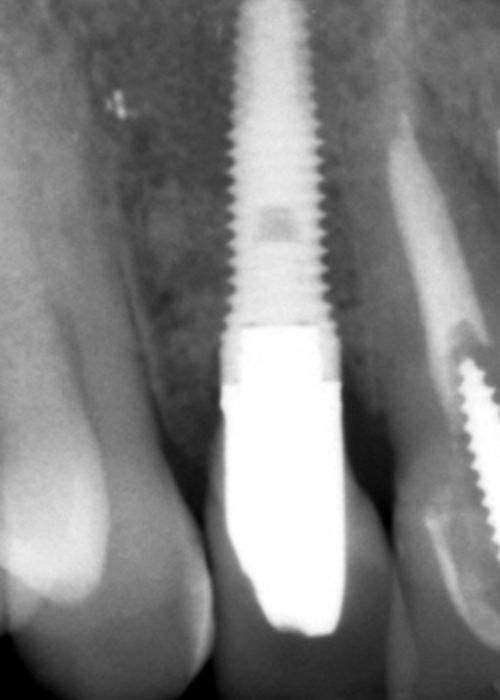

Implant explantation poorly positioned in an aesthetic sector and subsequent regeneration with block grafting. Clinical case

Explantación de implante mal posicionado en sector estético y regeneración posterior con injerto en bloque